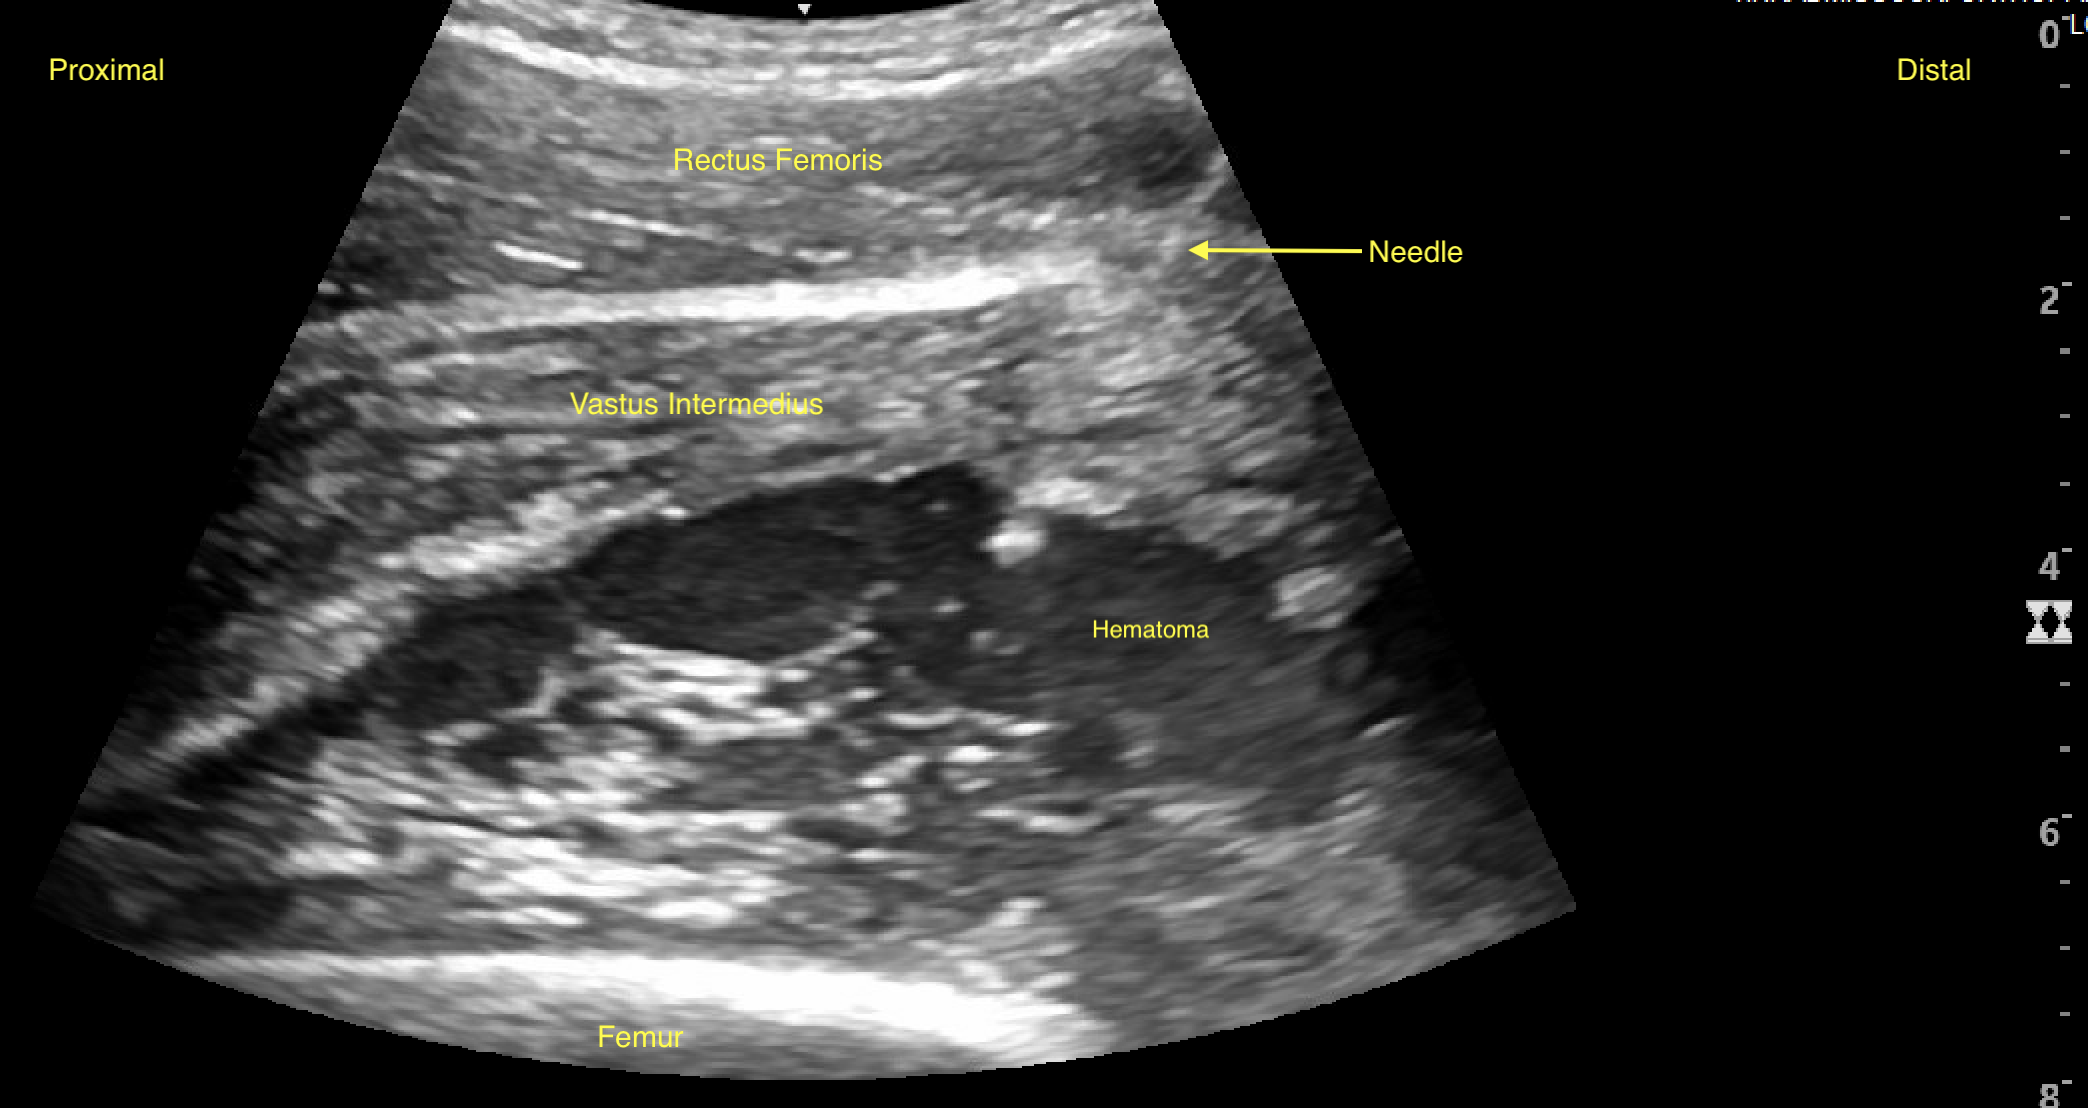

Labeled long axis view of the right quadriceps muscle with hematoma two weeks after the initial injury.

Clinical Vignette: 22-year-old male Division I basketball player presents to clinic for re-aspiration of large quadricep hematoma that was sustained during a basketball game about four weeks prior. Initial aspiration was completed two weeks prior. Athletic trainer stated right thigh swelling had recurred, and the patient was having limited knee flexion.